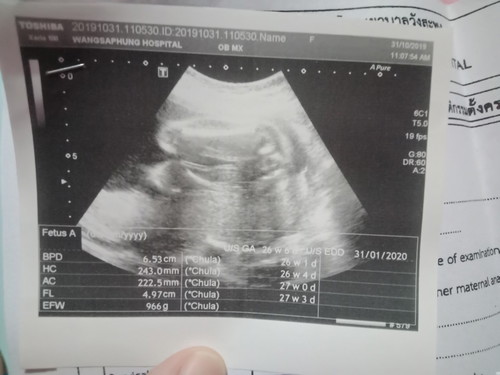

ช่วยดูหน่อยจ้า หญิง หรือ ชาย

ตอนนี้ได้ 30+5 แล้วจ้า กำหนอดคลอด 31 มกราคม

น่าจะหญิงค่ะแม่ไม่เห็นจู๋โผล่

เหมือนจะเห็นกลีบ น่าจะหญิงค่ะ